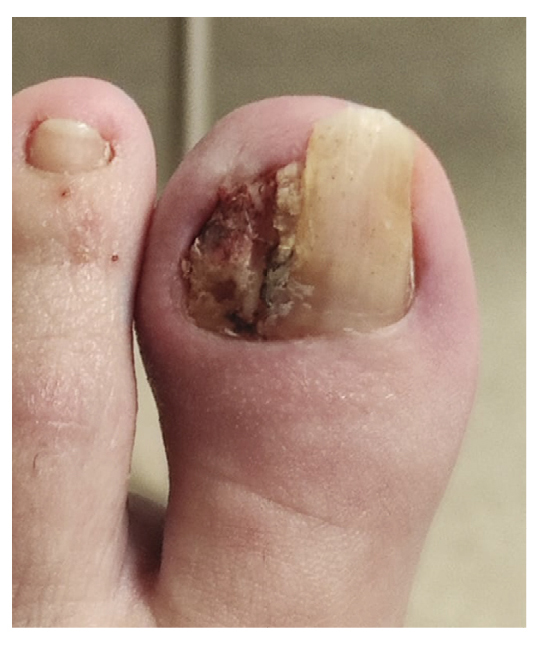

La paciente refiere proceso de inicial de onicocriptosis de 7 meses de evolución (septiembre de 2022), en el borde medial del primer dedo del pie izquierdo, con la presencia de tejido de granulación ungueal en dicho borde, el cual le produce dolor e inflamación digital (Figura 1). La paciente recibe tratamiento por su podólogo que consiste en quiropodia y limpieza del canal; se pautan posteriormente curas diarias con mupirocina para la lesión. Existe mala evolución de la lesión en los días siguientes con aumento de dolor y sensibilidad al tacto. Se modifica el tratamiento pautando amoxicilina/ácido clavulánico 875/125 mg, 1/8 h junto con el uso de analgésicos orales (Figura 2). La paciente continúa con mala evolución sintomatológica y acude a su centro de salud donde se realiza radiografía con la cual se descarta la presencia de infección profunda (osteomielitis).

Figura 2. Progresión clínica tras tratamiento ATB y analgésico.

Tras empeoramiento del cuadro clínico, el 14 de noviembre de 2022 se realiza en su centro de salud la retirada parcial de la placa ungueal lateral del pie izquierdo junto con raspado, retirando tejido hiperqueratósico y de granulación. El procedimiento es repetido 48 h más tarde (16 de noviembre de 2022) por no haber retirado toda la lesión (Figura 3), cambiando el tratamiento antibiótico a anaclosil 500 mg 1/6 h y posteriormente a ciprofloxacino 500 mg 1/12 h durante las siguientes semanas.